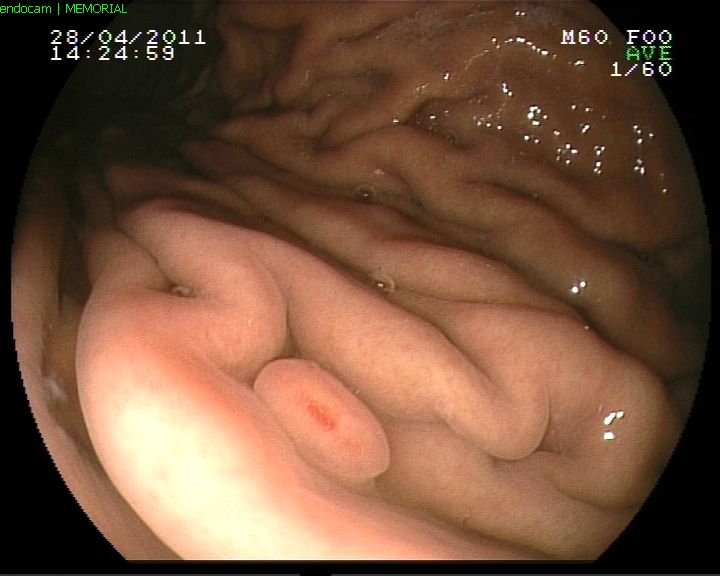

Kolonda divertikül